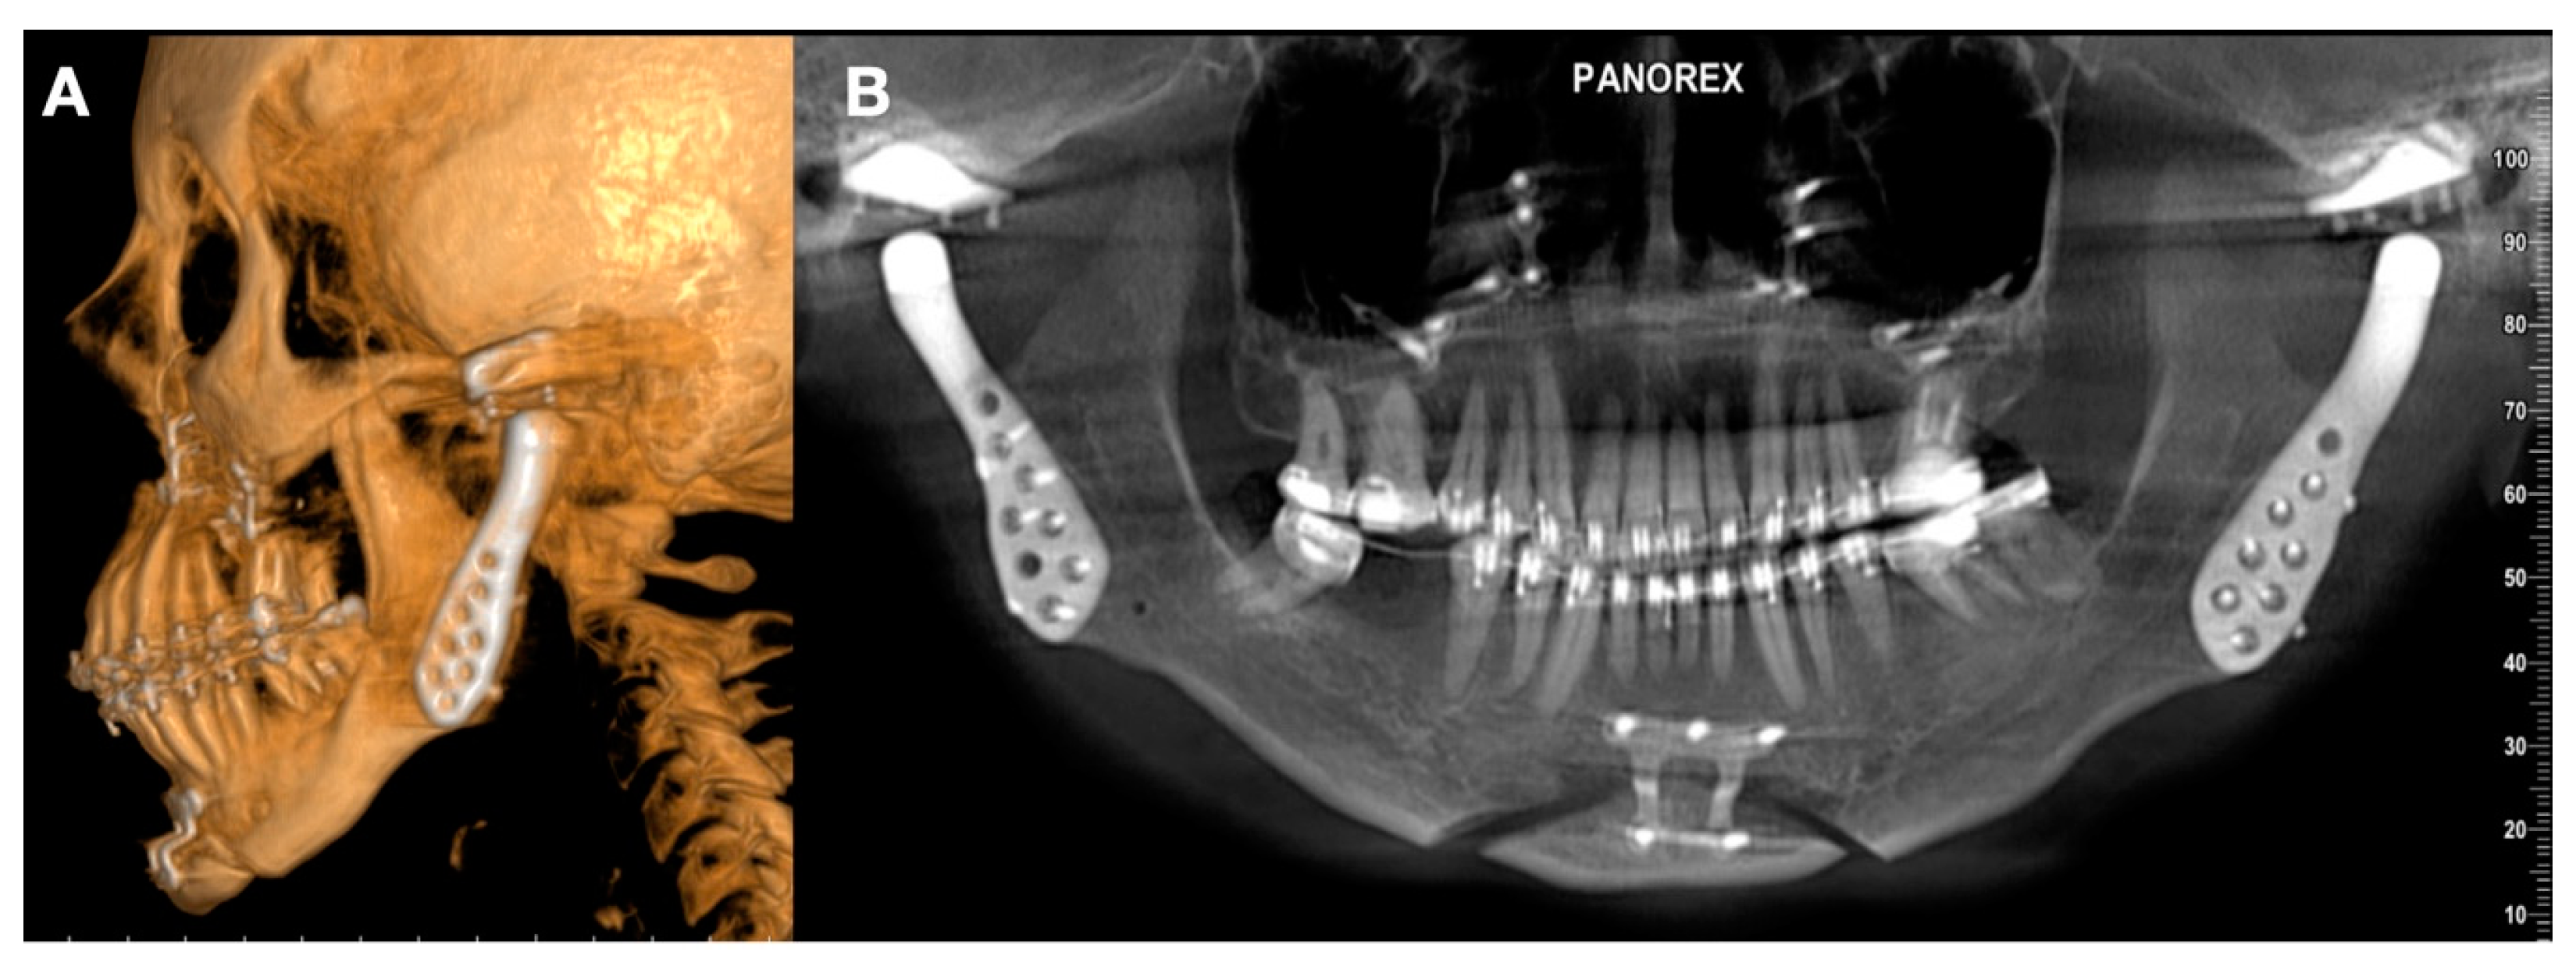

- Malformations, Pathology, or Trauma of the Mandibular Condyle

- Surgical specification for the operation; complementary surgery;